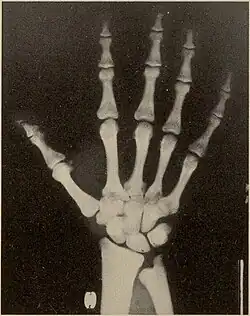

La picnodisostosis es una enfermedad hereditaria rara que pertenece al grupo de las enfermedades por depósito lisosomal. Está ocasionada por la mutación de un gen localizado en el cromosoma 1 humano que codifica la enzima catepsina K. Esta sustancia es producida en condiciones normales por los osteoclastos del hueso y tiene la finalidad de hacer posible la división de las proteínas que forman la matriz ósea. La deficiencia de catepsina K provoca entre otros síntomas, estatura baja, fragilidad de los huesos, fracturas espontáneas, malformaciones del cráneo y dentales.[1]

| Síntomas | cabeza grande y frente alta, huesos faciales poco desarrollados y dedos de manos y pies cortos. | |